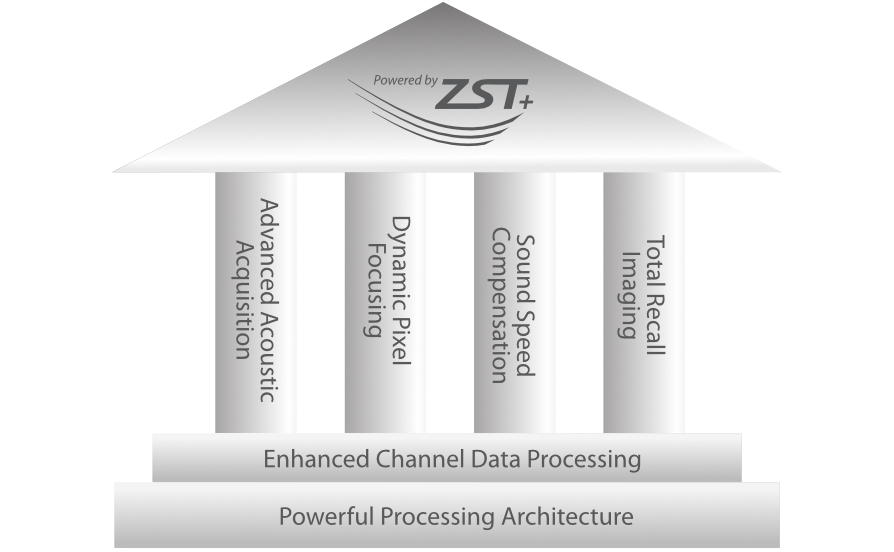

Solusi lengkap yang Didukung oleh ZST +

Platform ZST+ merupakan inovasi luar biasa yang mewakili evolusi ultrasound. Mentransformasikan metrik ultrasound dari pembentukan cahaya konvensional menjadi pemrosesan berbasis channel data. Mengatasi batasan kompromi tradisional antara resolusi spasial, resolusi temporal, dan keseragaman jaringan, menghadirkan mutu gambar yang luar biasa untuk solusi pencitraan tak terbatas dengan peningkatan secara berkelanjutan.